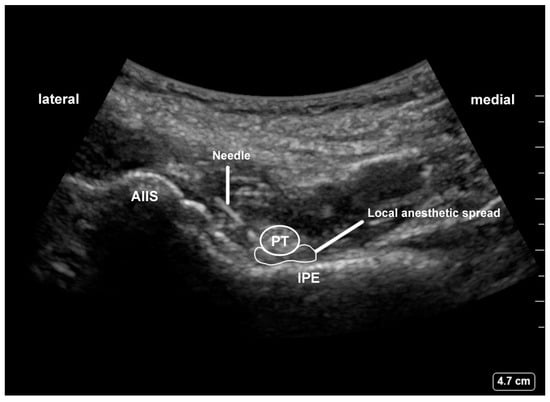

2.3. Interventions